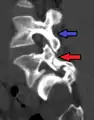

Anterolisthesis L5/S1. Blue arrow normal pars interarticularis. Red arrow is a break in pars interarticularis.

Computed Tomography (CT)

Computed tomography can be helpful in evaluating bony vertebral abnormalities, such as fractures.[33] This can be helpful in determining if the fracture is a new, old, and/or progressing fracture.[33] CT use in spondylolisthesis evaluation is controversial due to high radiation exposure.[34]